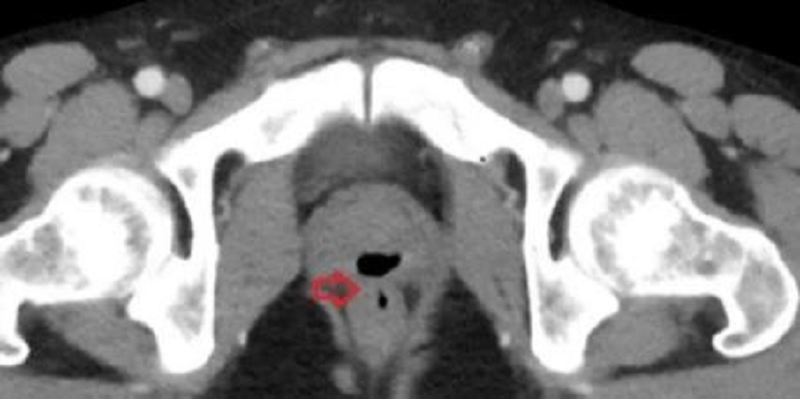

Ao ser submetido a um exame de toque retal, a equipe médica descobriu que o paciente tinha problemas na parede retal e uma infecção no trato urinário. Outros exames identificaram uma fústula, passagem anormal entre a uretra e o reto. Ele passou por uma cirurgia e, segundo os médicos, as complicações podem ter sido causadas por um cateter que recebeu quando esteve em coma.